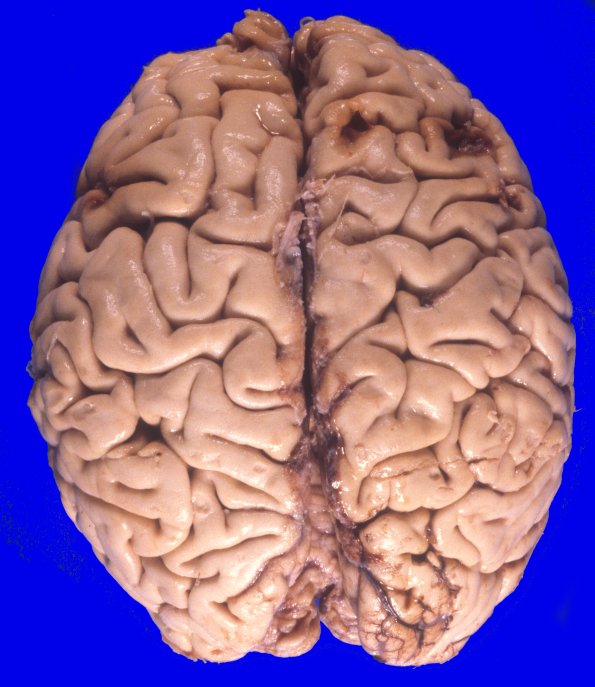

Case 17 History ---- The patient is a 44yo male with a past medical history significant for alcohol abuse and schizophrenia. He suffered a severe head injury in December 1980 when he was hit on the head with a baseball bat. Six months later he developed a poorly controlled seizure disorder characterized by prolonged generalized tonic -clonic seizures. ---- 17A1 The dorsal aspect of the cerebral hemispheres shows contusions in multiple places, an unusual pattern of injury likely related to multiple blunt injuries to the superior skull surface.